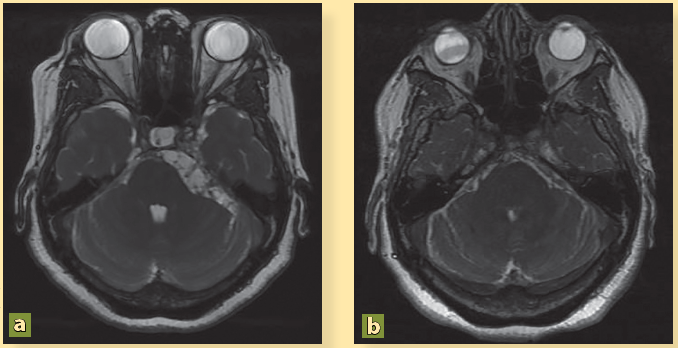

La paciente presenta mejoría clínica y es egresada por remisión de la cefalea y de las crisis convulsivas tras 16 días de estancia hospitalaria con indicaciones de continuar con esteroides vía oral y fármacos anticomiciales. Por iniciativa propia, la paciente no acudió a sus citas de seguimiento durante 4 años. Después, y debido a que ha presentado cefalea con intensidad 10/10, náusea y vómito constantes, desorientación y alteraciones del lenguaje, y varios episodios convulsivos, es traída por sus familiares al servicio de urgencias. Los familiares informaron que el tratamiento médico fue abandonado y optaron por una terapia de medicina naturista. Se ingresó la paciente y la nueva RM mostró persistencia de los cisticercos (figuras 2A, 2C, 3A, 4A) así como dilatación de los ventrículos (figura 5A). Se colocó una derivación ventrículo peritoneal (DVP) (figura 5B) y se inició nuevo tratamiento con albendazol (15 mg/kg), praziquantel (50 mg/kg) por 10 días, y dexametasona (8 mg/8h). Tras 40 días de estancia hospitalaria, se decidió su egreso con cita en la consulta externa.

La cisterna pontocerebelosa presenta lesiones quísticas múltiples (a), las cuales no se observan después del tratamiento cestocida (b).

Figura 3 Resonancia magnética secuencia FIESTA

Nótese la presencia de estructuras hipointensas quísticas en la cisterna bulbar, características de NCC (a). Después del tratamiento con fármacos cestocidas ya no se observan dichas lesiones quísticas (b).

Figura 4 Resonancia magnética secuencia FIESTA

El resultado del tratamiento fue parcial y la paciente requirió de 8 ciclos de albendazol para poder inactivar la NCC. En la RM de 2019 se mostró la remisión total de los parásitos y la ausencia de hidrocefalia (figuras 2B, 2D, 3B, 4B). Actualmente la paciente se mantiene estable, sin cefaleas, ni eventos convulsivos y con un buen funcionamiento de la DVP.